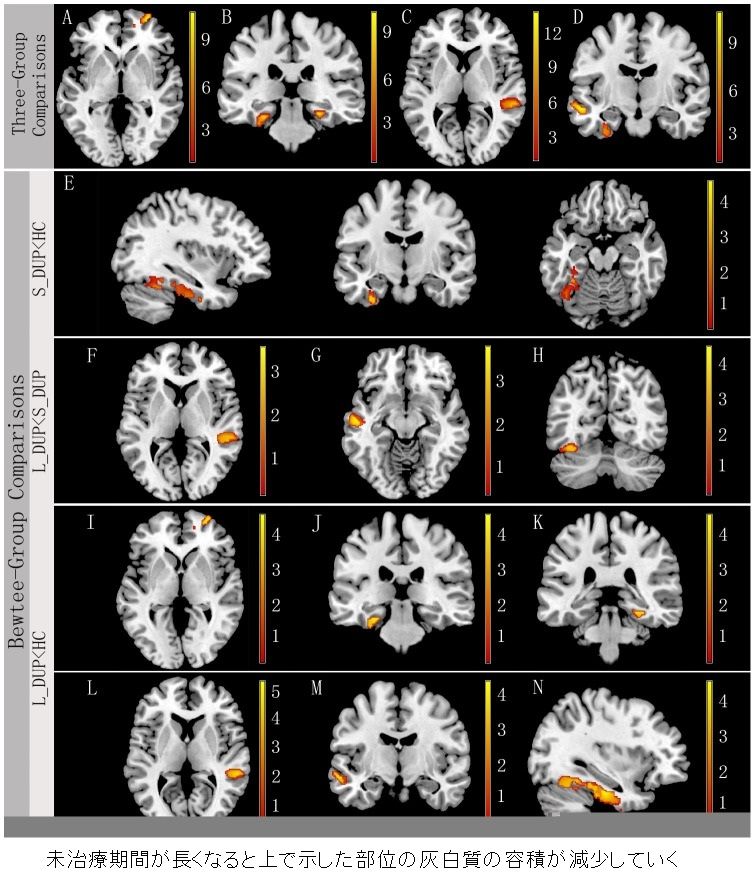

場末p科病院の精神科医のblog 統合失調症